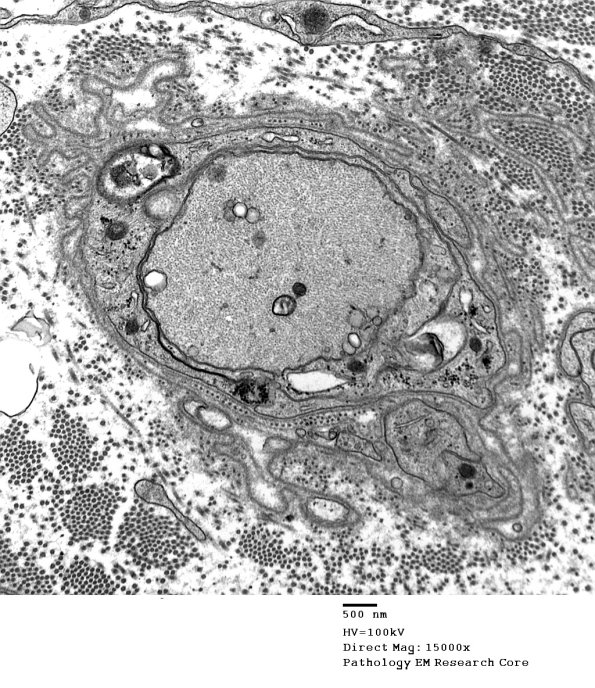

Perhaps the earliest example of remyelination. (electron micrograph)